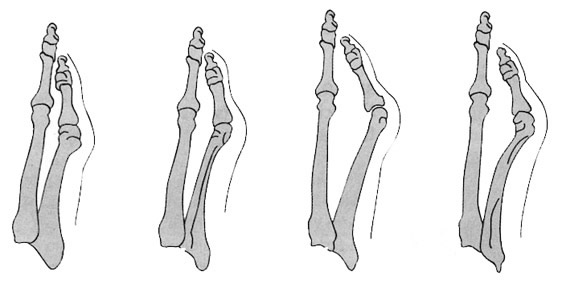

A láb kisujja (az V. ujj) ráhajlik a mellette levő (IV.) ujjra. Ez a ráhajlás lehet veleszületett, de gyakrabban szerzett lábdeformitás.

Ha az ujjaknak a hordott cipőben nincs elegendő hely adva az elhelyezkedéshez és a járás közbeni előremozduláshoz a cipőn belül az ellépés fázisában, mert túl keskeny, hegyes a cipő orrformája akkor a kisujj „hozzá idomul” a cipő orrformájához.

Magas sarkú , hegyes orrú cipő rendszeres, egész napi viselése fokozza a láb kisujjára ható oldalirányú nyomást, egyúttal a kisujj alatti (az V. metatarsus feje) alatti területre a talaj felől is túlterhelés lép fel. A láb kisujja az állandó nyomások hatására tartósan elferdült állapotot vesz fel.

Az elferdült állapot fokozódása - ami rendszerint széles lábon hordott extrém hegyes urrú cipő hordásakor következhet be – a kisujj ráfordulása a mellette lévő IV. ujjra.